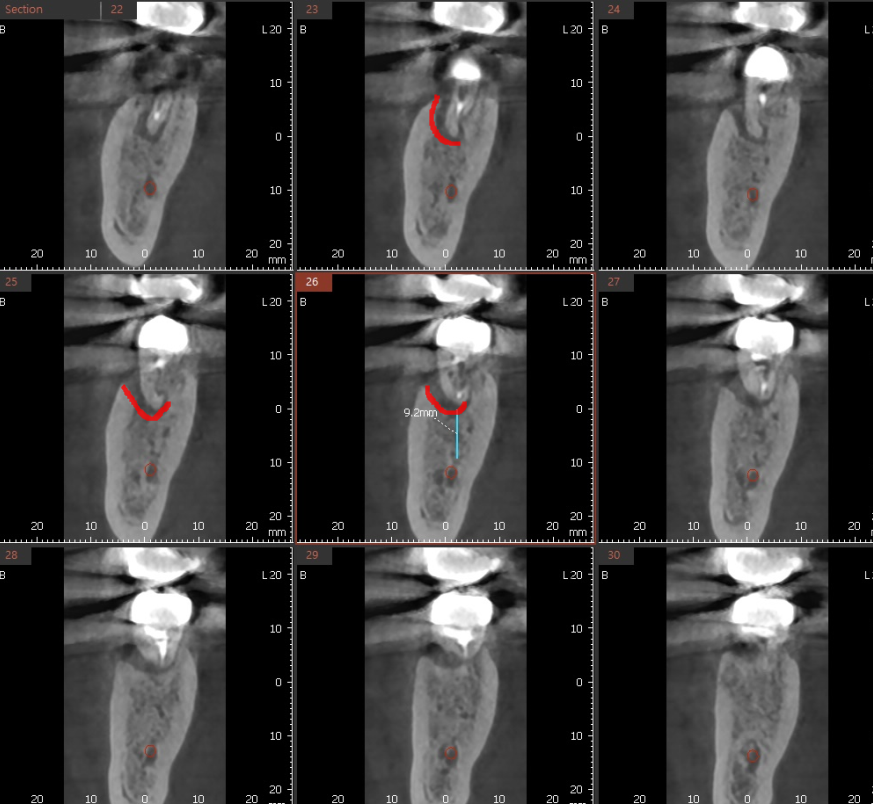

또한 ct에서 6.4mm 보이시죠~?

신경관과 치아 뿌리 사이 간격이 6mm라는 뜻입니다.

어금니 임플란트는 최소 8-10mm를 식립하는데

잇몸뼈를 녹일 수록 위험 부담도 높아지는거죠~

물론 네비게이션 임플란트 기술을 사용하면

최적의 식립 위치를 확인할 수 있기야 하지만

신경관과 가까워 신경손상 가능성이 있다~

이런 주의사항을 말씀드릴때마다

환자분들은 얼마나 놀라시겠습니까

수술 하는거 그 자체로도 공포이실텐데요.

240501

빨간색 동그라미가 신경관인데

ct를 통해 1차 분석

2차로 네비게이션 임플란트 기술 활용

신경관을 피해 안전하게 임플란트 수술 완료하였습니다.